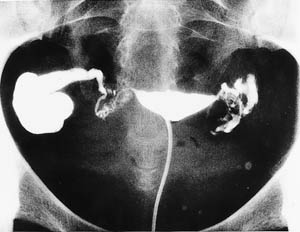

أشعة الرحم الصبغية

Hysterosalpingography (HSG)

طريقة الأشعة تعتمد على

إدخال مادة ملونة من خلال أنبوب يدخل في عنق الرحم يدفع من خلاله

المادة الملونة، وتؤخذ عدة صور شعاعية مع مراقبة مباشرة لمرور السائل

الملون على الشاشة، وإذا كان هناك انسداد في قناة فالوب مثلاً فلن

تتمكن المادة الملونة من المرور.

وبواسطة هذا الفحص

نستطيع الحصول على معلومات يمكن الاستفادة منها في معرفة حالة قناتا

فالوب (وجود انسداد كامل أو جزئي أو التصاقات)، ويمكن تلخيص المشاكل

التي نستطيع تشخيصها بواسطة هذا الفحص فيما يلي:

تشخيص أورام في تجويف

الرحم مثل وجــود ليف (Fibroid)

أو زوائــد لحمية (Polyps).

تشخيص انسداد مع توسع

قنوات فالوب (Hydrosalpinx).